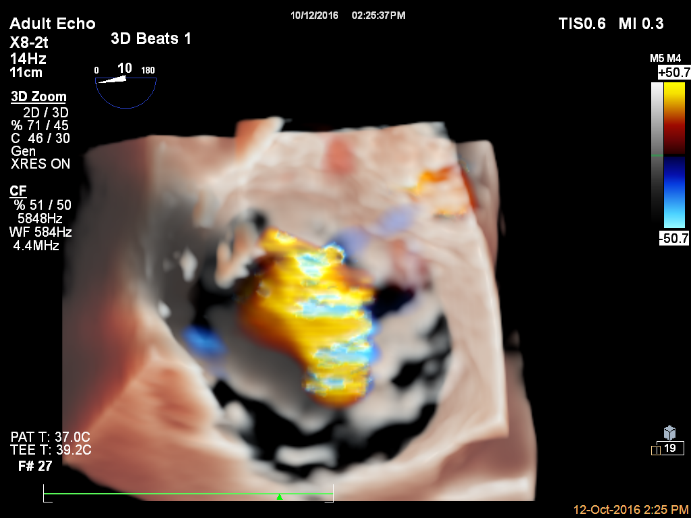

回顾性分析61例重度MR患者在TMVR术前和术后6个月行经食管三维超声心动图检查(所有手术均采用第一代MitraClip系统进行)。其中:功能性MR(FMR)(n=45)和器质性MR(OMR)(n=16)。使用三维超声心动图软件MVQ对MV几何结构进行量化分析。随访术后6个月时的缩流颈面积(VCA)确定两个结果组:VCA<0.6cm²(MR<0.6)为效果良好组和VCA≥0.6cm²(MR≥0.6)为复发组。

研究患者中34%(21/61)出现复发MR。在FMR患者中,在术前基线检查时发现MR<0.6和MR≥0.6在tenting index(穹隆指数)(1.13 vs 1.23,P=.004)、tenting volume(穹隆容积)(2.8 vs 4.0 ml,P=.04)、左室舒张末期容积指数(LVEDVi)(68.0 vs 99.9 ml/m²,P=.001)和VCA(0.71 vs 1.00 cm²,P=.003)方面存在显著差异;在OMR患者中未发现MR复发相关的重要决定参数。多变量分析显示左室舒张末期容积指数是MR复发的最强独立决定因素。区分MR<0.6和MR≥0.6的截点值为穹隆指数1.185(曲线下面积0.79)和左室舒张末期容积指数88ml/m²(曲线下面积0.76)。